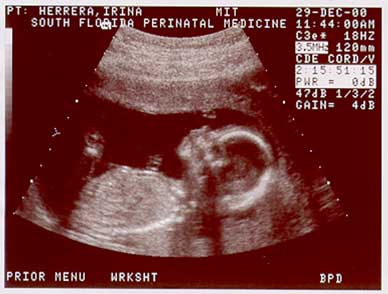

These images show the baby at 17wks. (Dec. 29, 2000) |

Image sequence 2 of 3 |

![]() Baby at 17 weeks, Image sequence 3 of 3 |